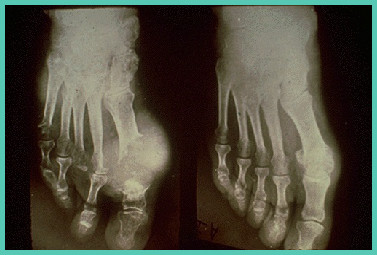

痛风石逐渐增大后,其外表皮肤可能变薄溃破,形成窦道,排出白色牙膏样的尿酸盐结晶物,经久不愈。发生在手足附近的结石,常影响关节活动,导致慢性关节肿痛、僵直和畸形, 甚至骨折。